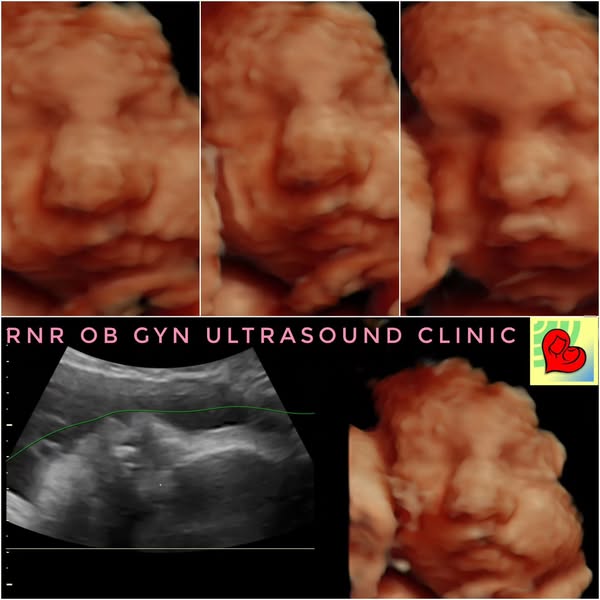

💕A 3D4D 5D Ultrasound in Superior 5D HD LIVE™ format offers a first glimpse of the baby’s features, which can be emotionally significant for expectant parents and can enhance their bonding experience! 🤱

It also helps in assessing fetal development and provides parents with a visual connection to their baby before birth.🥰

💕#5DUltrasound available at RNR OB GYN ULTRASOUND CLINIC, Perez Blvd, Dagupan City!

💕Here are images of a pretty baby girl both her 5D images and her cute newborn photos!